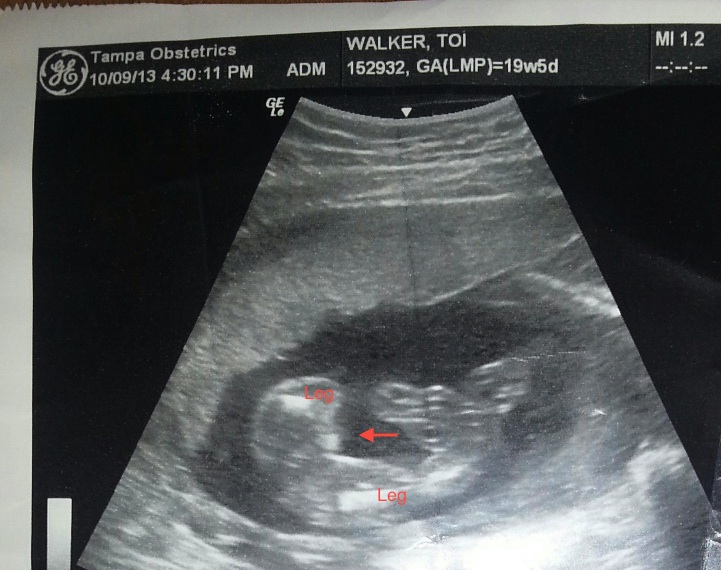

I'm so confused! I had my 20 week anatomy scan and the ultrasound tech was sure it was a boy. Here are the pics I received at that scan:

Attachment 14833